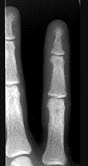

女,41岁,慢性肾功能衰竭,请结合图像,选出最可能的诊断()A.白血病B.甲状旁腺功能亢进C.地中海贫血D.镰状细胞贫血E.骨关节结核

问题 女,41岁,慢性肾功能衰竭,请结合图像,选出最可能的诊断()

选项 A.白血病 B.甲状旁腺功能亢进 C.地中海贫血 D.镰状细胞贫血 E.骨关节结核

答案 B